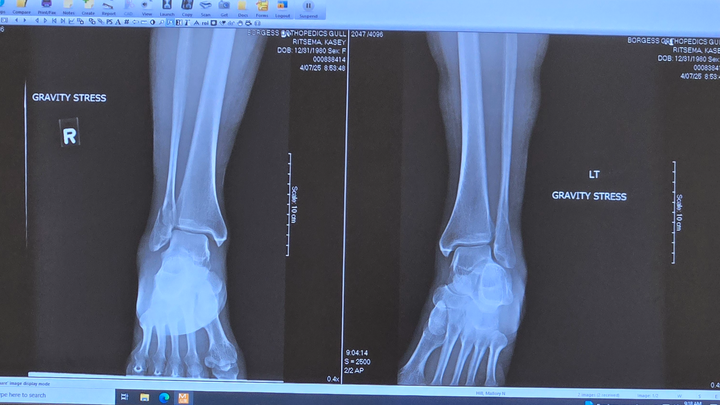

Hi everyone. My name is Kasey Ritsema. On Monday, March 31st, 2025, I had an unbelievable accident. I fell and broke both of my ankles and sprained my left knee. I went to see my orthopedic surgeon yesterday morning, April 7th, 2025. I was told my options were to have surgery to fix them or not. If I chose not to go through with the surgery, when I started to walk again on my own without the support of the orthopedic boots, every step that I took was going to feel as if I was about to fall because of the way they would heal. I definitely don't think that would be a very good quality of life, constantly feeling as if I were going to fall. As much as I was hoping to avoid surgery, I agreed to have the surgery done. They are putting plates and screws in my leg to fix my ankles on Wednesday, April 9th, 2025.